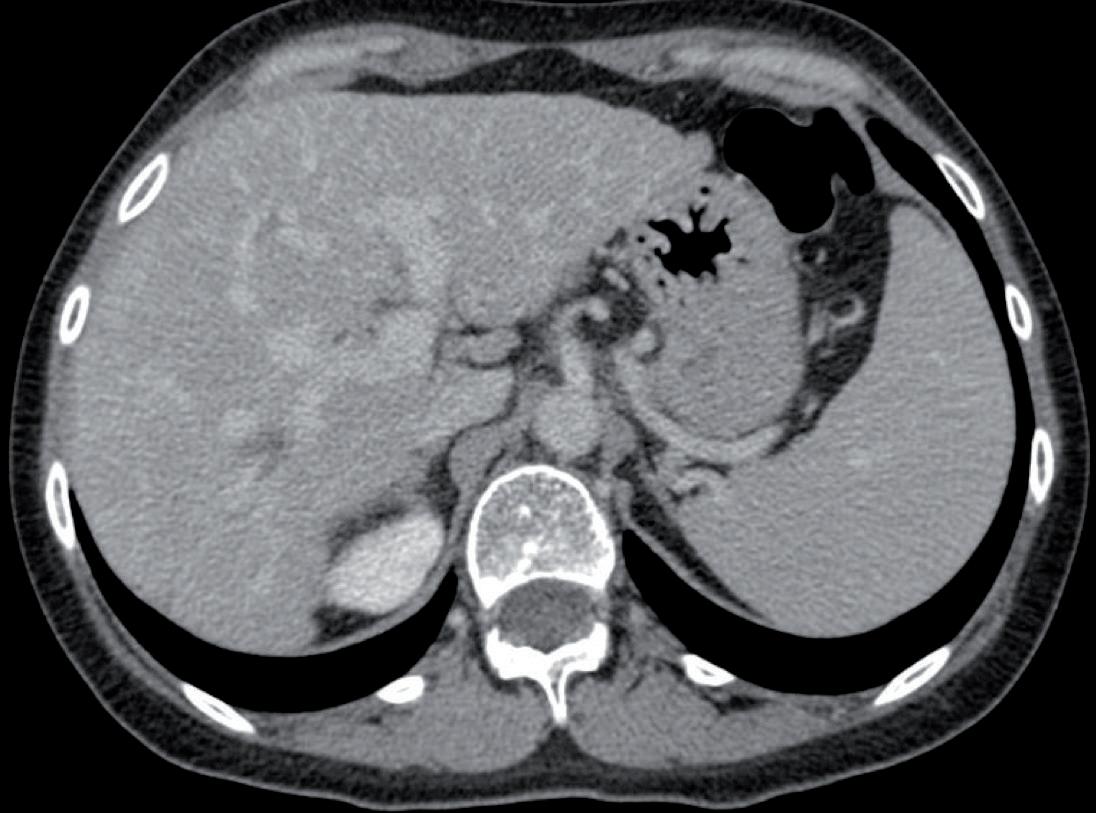

Nel 2022-2024, la paziente riceve chemioterapia secondo schema TEX (epirubicina, docetaxel, capecitabina) per 4 cicli, per poi proseguire con docetaxel + capecitabina fino a Gennaio 2024 (21 cicli totali). Durante il trattamento si osserva risposta parziale in tutte le sedi note di malattia, con successiva progressione cerebrale documentata da RMN nel Febbraio 2024. Nel Febbraio 2024, a seguito della progressione encefalica evidenziata da RMN – con la comparsa di multiple lesioni cerebellari, parietali e occipitali sinistre (figura 1) – viene avviato il trattamento con trastuzumab deruxtecan (T-DXd) alla dose di 5,4 mg/kg ogni 21 giorni. La scelta terapeutica si basa sulla confermata espressione HER2 low del tumore primitivo, identificata all’esordio e successivamente confermata tramite biopsia della malattia metastatica. Fin dalle prime somministrazioni, la paziente mostra una buona tolleranza al trattamento. Dopo i primi due cicli, non vengono riferiti effetti collaterali rilevanti, e il quadro clinico si mantiene stabile. Con il progredire della terapia, dopo quattro cicli, si osserva l’insorgenza di una sindrome mano-piede di grado 1-2, gestita con terapia sintomatica senza necessità di modifiche posologiche.

Alla prima valutazione strumentale dopo sei cicli, la TC documenta una stabilità dei secondarismi encefalici e ossei, accompagnata da una buona risposta epatica, suggerendo un’efficacia precoce del trattamento. Parallelamente, la paziente mantiene un buon perfor-

La stabilità encefalica persiste anche dopo dieci cicli, con una riduzione parziale delle lesioni epatiche, segno di un beneficio clinico duraturo. Dopo dodici cicli, il trattamento continua a essere ben tollerato: non emergono eventi avversi significativi, e la funzione cardiaca risulta conservata, con una frazione di eiezione (FE) del 67%.

Alla quattordicesima somministrazione, la rivalutazione mediante TC mostra una sostanziale stabilità della malattia epatica e ossea (figura 2). Tuttavia, la RMN encefalica evidenzia un incremento dimensionale della lesione cerebellare sinistra, associata a edema perilesionale (figura 3). Pur in assenza di sintomi neurologici, si decide di avviare una terapia corticosteroidea a scalare per il controllo dell’edema.

Figura 1. A livello emisferico cerebellare a destra lesione puntiforme di circa 1 mm.

In sede paravermiana superiore a destra lesione di circa 9 mm.